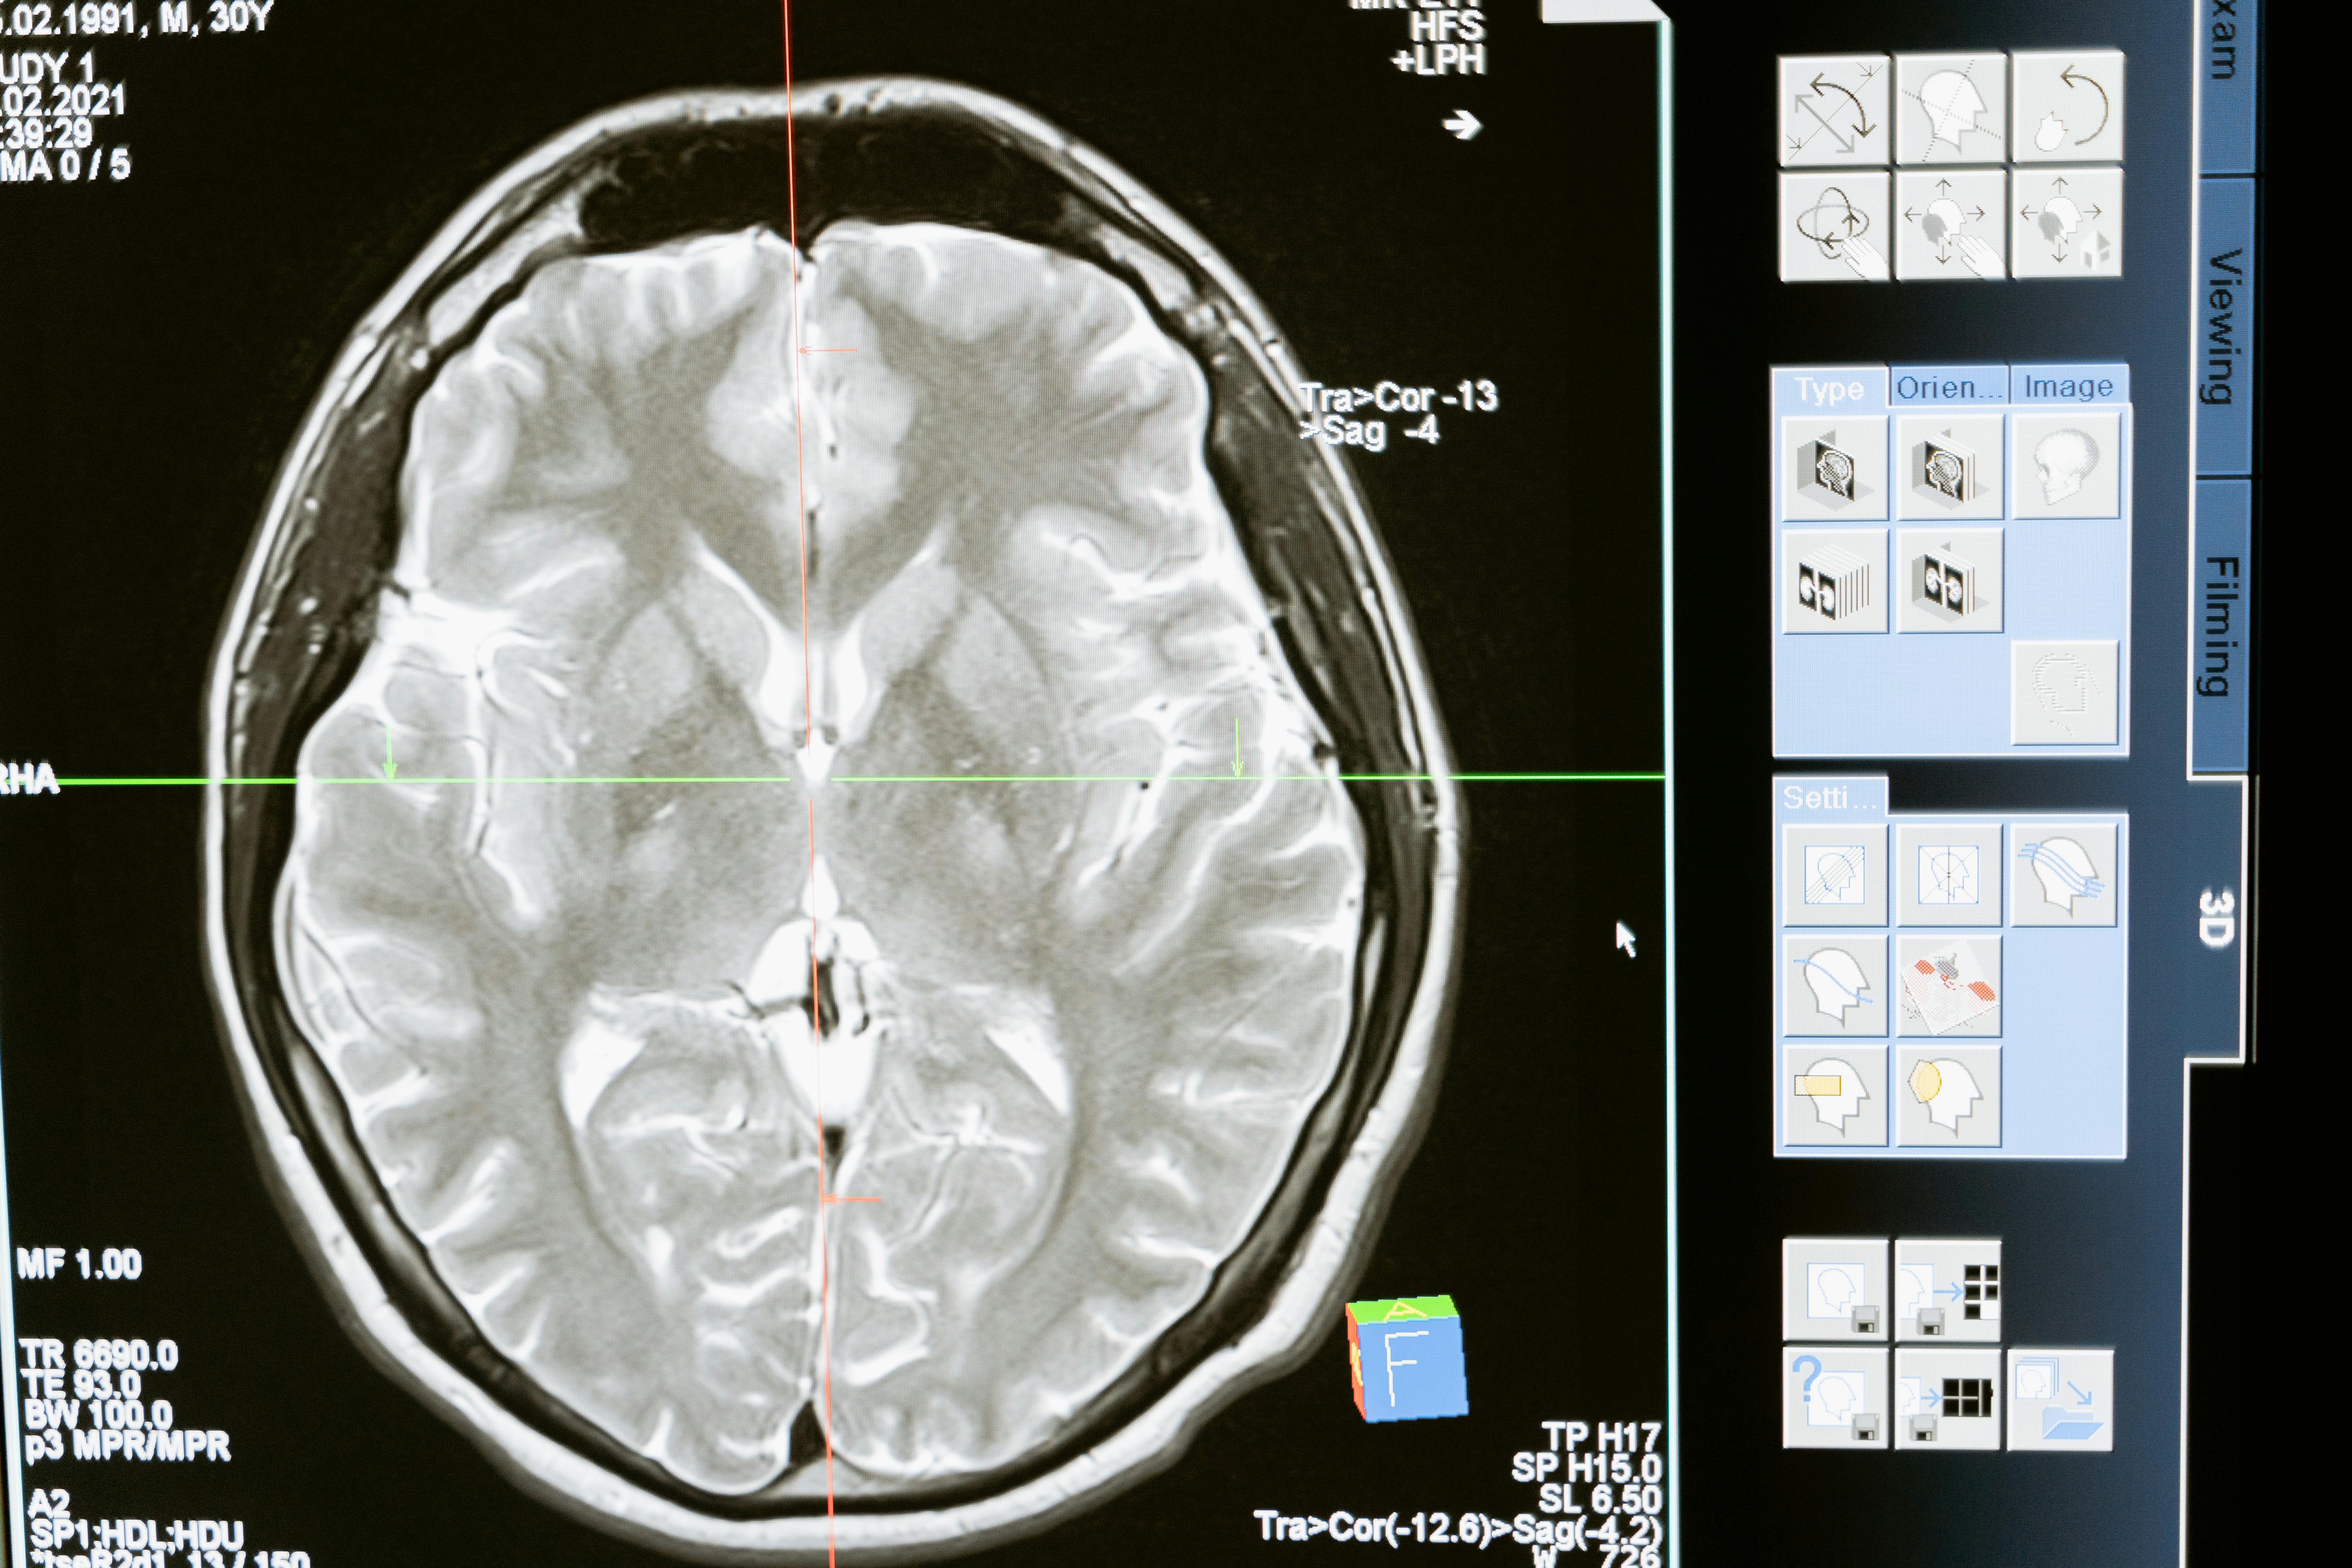

뇌경색 완치율, 치료, 후유증, 재발

뇌경색(허혈성 뇌졸중)은 혈전이 뇌로 가는 혈류를 차단할 때 발생합니다. 치료 효과와 회복률은 치료의 신속성과 종류에 크게 좌우됩니다.